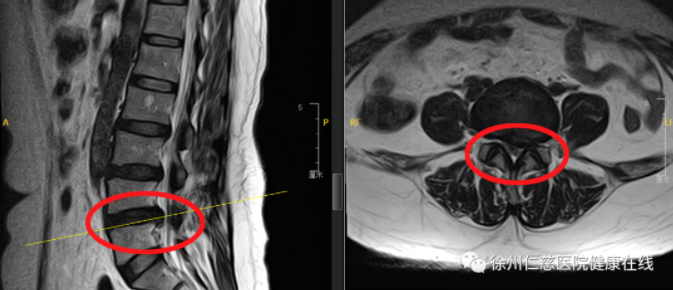

“查看影像学检查结果后,诊断患者主要是腰椎L4/5处向左侧的突出严重压迫神经根,这才导致左腿剧烈的麻木、疼痛,需尽快手术去除突出物,解除对神经根的压迫。”脊柱外科尚军主任带领医疗小组讨论、制定手术方案,为进一步降低手术风险,决定在3D显微镜这一大利器的加持下为李阿姨解除病痛。